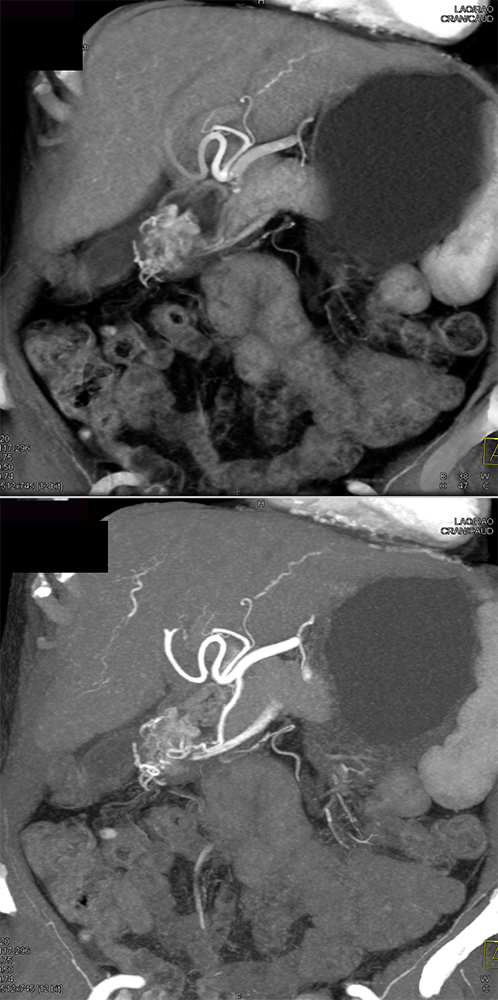

Suspected GI Bleed ![]() |

“In our patient, the findings of prominent mucosal folds extending from the pylonic channel on upper gastrointestinal series and the thickened antral wall on CT scans correlate well with the known pathologic appearance of gastnic antral vascular ectasia. Histologically, antral thickening results from a combination of foveolar and fibromuscular hyperplasia. Grossly, the antral fold prominence appears to result from bunching of the mucosa in the thickened, hypercontractile antrum.” Gastric antral vascular ectasia ("watermelon stomach"): radiologic findings. Urban BA, Jones B, Fishman EK, Kern SE, Ravich WJ. Radiology. 1991 Feb;178(2):517-8. |

“Gastric antral vascular ectasia primanily affects women (9:1 female-to-male ratio) aged 56-76 years, and is associated with liver cirrhosis (37%) and achlorhydnia (35%). The usual symptoms are iron-deficiency anemia and melena due to chronic gastrointestinal bleeding from the dilated, superficial, and easily traumatized vessels. Antrectomy is curative, but endoscopic treatment with heat probes or lasers has shown promise.” Gastric antral vascular ectasia ("watermelon stomach"): radiologic findings. Urban BA, Jones B, Fishman EK, Kern SE, Ravich WJ. Radiology. 1991 Feb;178(2):517-8. |